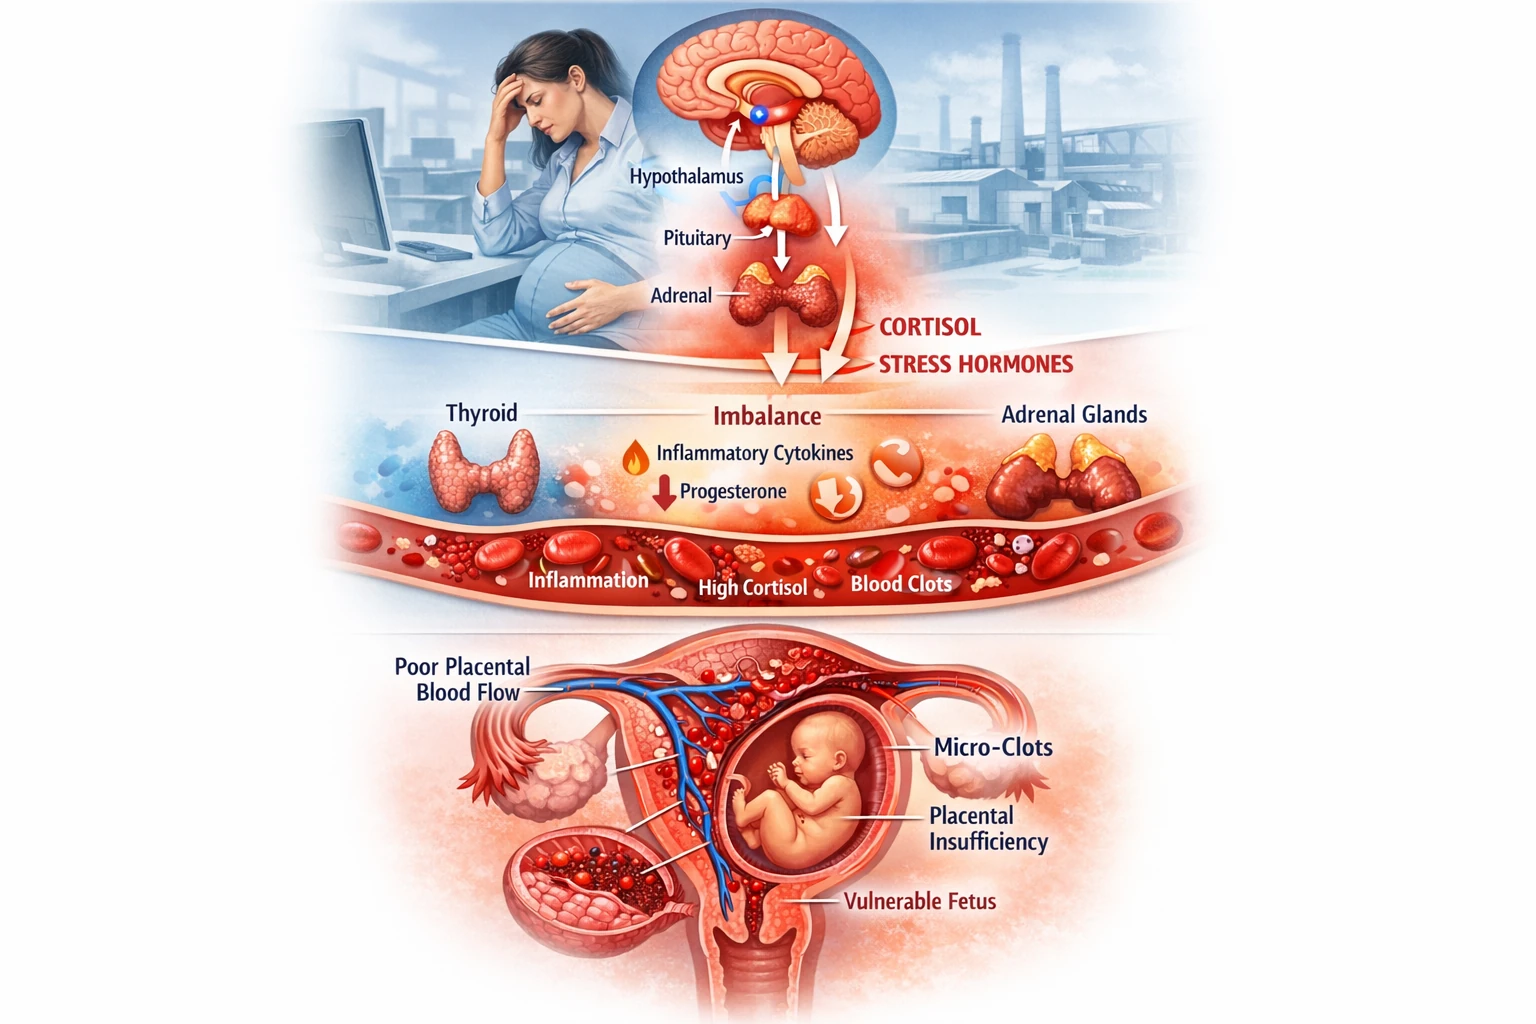

✅ در دوران بارداری، سیستم ایمنی مادر تغییر میکند و همین موضوع خطر عبور باکتری از جفت و درگیری مستقیم جنین را افزایش میدهد.

عفونت مادرزادی لیستریا میتواند منجر به:

- آسیب مغزی جنین (مننژیت یا انسفالیت)

- سپسیس نوزادی

- زایمان زودرس

- سقط یا مرگ داخل رحمی

🔹 هرچه عفونت در سهماهه اول یا دوم رخ دهد، احتمال آسیبهای عصبی شدیدتر خواهد بود.